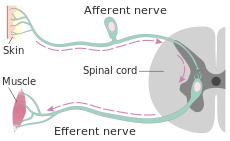

- Central Nervous System – any condition that affects or lowers the conscious level.

- Peripheral Nervous System – any condition that affects the peripheral neural system (e.g. Guillain-Barré syndrome (GBS), nerve or spinal injury)